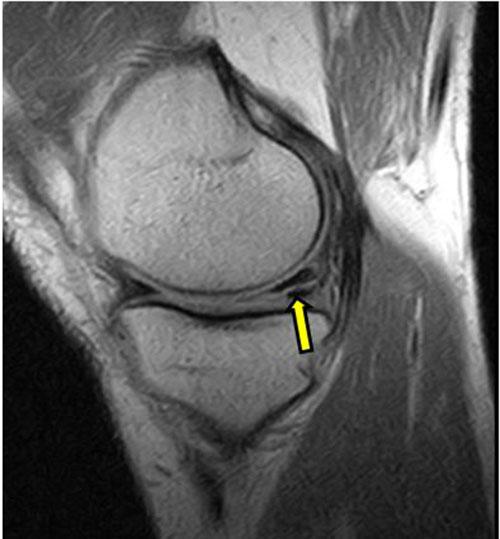

Sagittal intermediate-weighted fat-saturated image shows a typical horizontal-oblique meniscal tear of the posterior horn reaching the undersurface of the meniscus (arrows).